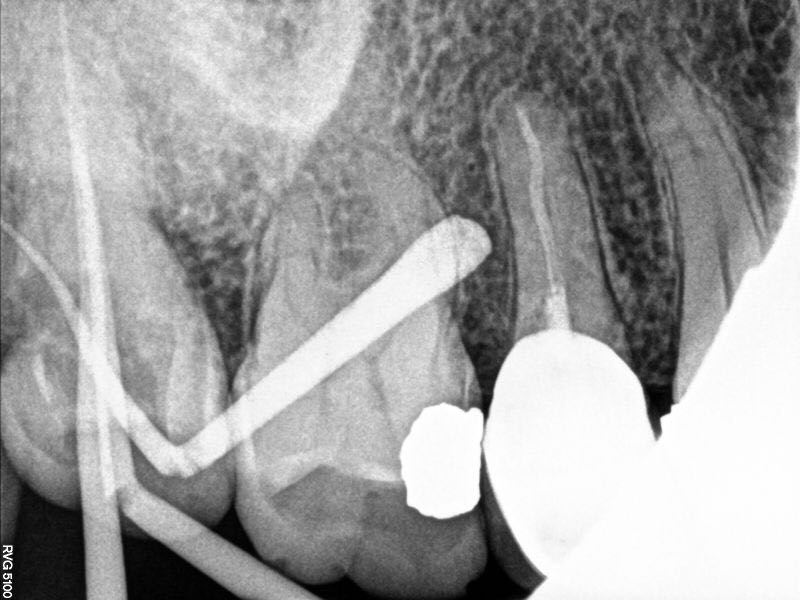

插针片可见远颊根s型弯曲